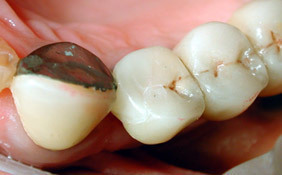

Les inlays en céramique (ou incrustations en céramique) permettent de restaurer les dents dont le délabrement est important et inesthétique.

L'inlay en céramique constitue un excellent compromis solidité/esthétique/respect des tissus dentaires de par sa nature céramique et la qualité de son collage.

L'inlay permet dans de nombreux cas sur dents vivantes d'éviter la couronne prothétiquecéramique qui nécessite le retrait complet de la coque d'émail de la dent dont la fonction première est de protéger la dent.

L'inlay ne reconstitue "que" ce qu'il manque de la dent.